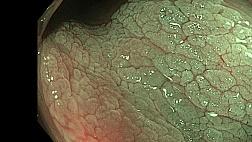

8. 18:53 АКАДЕМИЯ ЭНДОСКОПИИ: Применение технологии BLI/LCI в колопроктологии

21. 25:57 АКАДЕМИЯ ЭНДОСКОПИИ: Технологии эндоскопической визуализации в диагностике колоректальных неоплазий

22. 24:06 Выявление предраковых изменений слизистой оболочки толстой кишки с использованием технологии I-Scan

КАЧЕСТВЕННАЯ КОЛОНОСКОПИЯ – «ЗОЛОТОЙ» СТАНДАРТ ДИАГНОСТИКИ ЗАБОЛЕВАНИЙ ТОЛСТОЙ КИШКИ

16:40 - 16:50Новые оптические технологии в диагностике и характеристике полипов толстой кишки